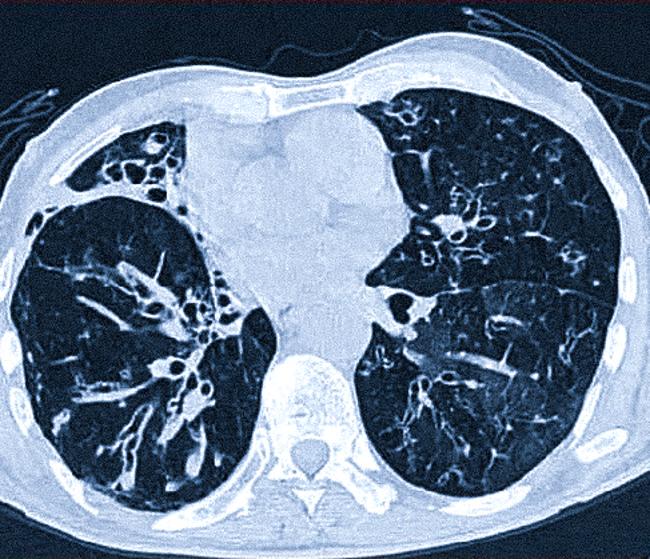

- Рентгенологические признаки: На рентгене могут проявляться изменения в легочных полях, а также увеличение сосудистого рисунка.

При интерпретации рентгенограмм органов грудной клетки у детей, термины «периваскулит» и «перибронхит» могут встречаться достаточно часто и требуют внимательного подхода. Периваскулит характеризуется воспалительными изменениями в окружающих сосудах, что может проявляться на рентгене в виде утолщения мягких тканей вокруг сосудов и изменением их очертаний. Это состояние может указывать на наличие инфекционно-воспалительных процессов в легочной ткани или более системные заболевания, такие как васкулиты.

С другой стороны, перибронхит связан с воспалением тканей, окружающих бронхи. На рентгене это проявляется в виде увеличенных перибронхиальных теней или утолщений стенок бронхов, что может свидетельствовать о наличии бронхитов, пневмоний или аллергических реакций. Важно отметить, что у детей данные изменения могут быть связаны с вирусными инфекциями, что требует тщательной оценки клинической картины и сопутствующих симптомов.

• изменения, отклонения в легочном рисунке и бронхах, в том числе исчезновение мелкой сосудистой сетки;

• увеличение корней легких и бронхов, их деформация;

• контур обоих или одного легкого нечеткий, стенки бронхов будут утолщены.